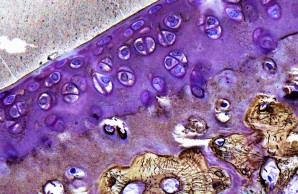

Project 4: Molecular bases of non-classical osteogenesis imperfecta

Project 4 focuses on the non-classical forms of osteogenesis imperfecta, which are characterized by low bone mass and skeletal fragility. We want to better understand the dynamic molecular processes during bone formation as well as identify key molecules and signaling pathways under pathophysiological conditions in order to establish causal therapies.

Project 8: Molecular understanding of fracture healing in early-onset low BMD disorders

Project 8 is investigating the extent to which specific gene variants influence the multi-stage process of fracture healing at the cellular and molecular level. In addition to genetic, metabolic and immunological aspects, the suitability of specific pharmacological interventions to improve bone regeneration is also being analyzed.

Project 9: Impact of specific gene variants on growth plate and articular cartilage in early-onset low BMD disorders

Project 9 covers the characterization of patients who suffer from skeletal dysplasia and/or osteoarthritis in addition to an early-onset low bone mineral density. To investigate the underlying pathomechanisms, histomorphometric and molecular analyses as well as disease modeling using pluripotent stem cells and mouse models are employed.